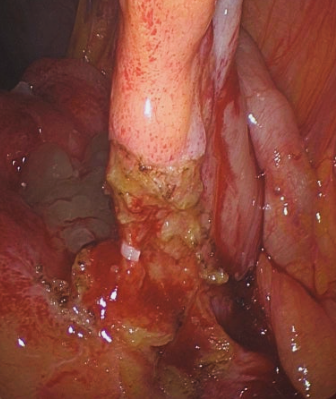

병원에서는 신체검사와 혈액 검사, 초음파 또는 CT 촬영 등을 통해 정확한 진단을 내립니다. 충수염으로 진단되면 대부분 충수돌기 절제술(맹장 제거 수술)을 통해 치료하며, 조기에 치료하면 합병증 없이 빠르게 회복할 수 있습니다.